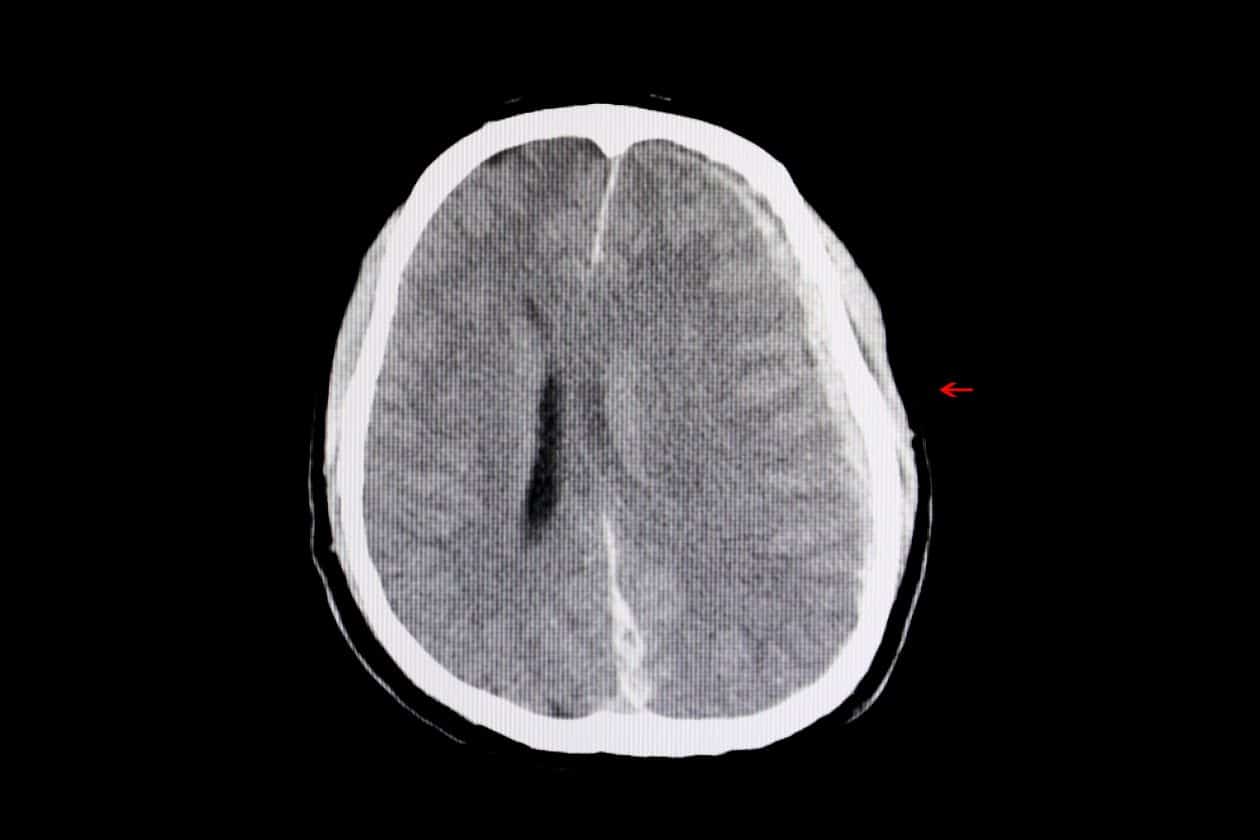

2. Hematoma subdural: Un hematoma subdural es una acumulación de sangre en el espacio entre el cerebro y el cráneo. Puede ser causado por un golpe fuerte en la cabeza y los síntomas pueden incluir dolor de cabeza, confusión y pérdida de conciencia.

3. Hemorragia intracraneal: Una hemorragia intracraneal es una acumulación de sangre dentro del cerebro. Puede ser causada por un traumatismo craneal grave y los síntomas pueden incluir dolor de cabeza, vómitos, debilidad y pérdida de conciencia.

4. Fractura craneal: Una fractura craneal es una ruptura en el hueso del cráneo. Puede ser causada por un traumatismo craneal grave y los síntomas pueden incluir dolor de cabeza, sangrado y pérdida de conciencia.